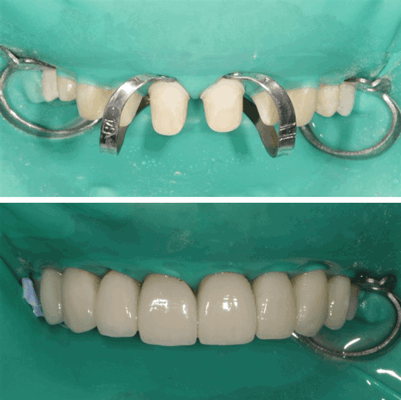

Приступаем к препарированию зубов

- минимально инвазивная обработка центральных резцов верхней челюсти с сохранением слоя эмали, необходимого для адгезивной фиксации керамических конструкций - виниров.

- видим атравматичную обработку зубов (нигде нет продкравливания и царапин десны),

- видим препарирование с сохранением анатомических контуров шейки зуба,

- четко просматриваемый уступ для будущих конструкций (коронок),

- на зубах видим огромные объемы предыдущих реставраций,

- видим цвет и структуру исходной культи зуба

На нижнем фото мы видим черновой вариант конструкций, на котором мы отработали эстетические и функциональные аспекты в полости рта. Фиолетовая масса между зубами - это масса для фиксации соотношения челюстей при наличии новых конструкций на передних зубах. Это положение обеспечивает контроль пространства необходимого для вправления диска в суставе и его правильного функционирования.

Теперь оцениваются все недочеты и вносятся коррективы. Ниже на фото вы видите примерку готовых конструкций полости рта. В этот момент происходит также оценка визуального восприятия пациентом.

Пациентке все понравилось. После работа отправилась обратно в лабораторию, и через несколько дней мы получили готовую работу.

Начинается следующий, очень важный этап: фиксация конструкций на зубы

На фото мы видим этап ортопедической реабилитации, фиксация постоянных конструкций в полости рта.

Обратите внимание на высокий уровень эстетики проведения работ доктором. У пациента во рту закреплен коффердам, который удерживается специальными кламмерами. Коффердам используется для изоляции рабочего поля от попадания слюны и влаги при выдохе у пациентов, потому что адгезивная фиксация не приемлет попадание влаги в любом количестве на поверхности фиксации виниров и коронок (т.к. впоследствии возможно развитие кариеса).

Минимальная травматичность слизистой при удалении остатков композита, используемого при фиксации. Возможность хорошей визуализации зоны контакта зуба с искусственной коронкой и возможность полировки этих переходов.

Очень кропотливая и длительная процедура. Но здесь мы с пациентом выходим фактически на финишную прямую лечения.

Э тап фиксации конструкции

Но этот этап и самый приятный, наша пациентка видит и чувствует новые зубы у себя во рту

После этого доделываем боковые зубы, и работа полностью может радовать нашу пациентку!